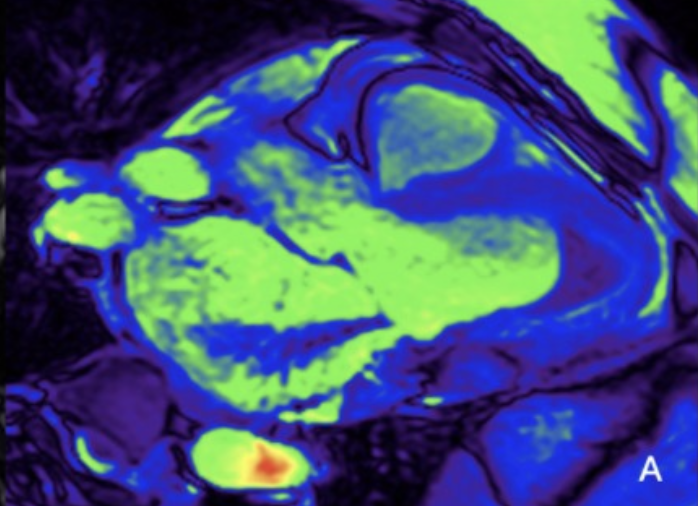

filling of the apical cavity of the left ventricle with fibrotic tissue, causing its obliteration

Subendocardial LGE with "V" morphology